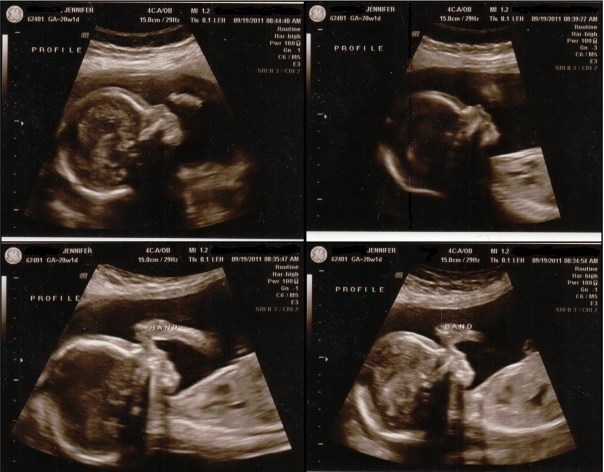

It’s a…

BOY!

This morning I had my 20 week ultrasound. There’s no doubt about it…there’s definitely a tiny little man in there! 🙂 Today he weighed 13 ounces and his heart rate was 145. Everything looked good, he’s perfect!

We brought Adaline with us and at first she was very excited to see the baby on the “tv”. After awhile she got bored with it and my mom took her out into the waiting room. I’m glad that we brought her, though. It seemed like she understood what was going on a little better being able to see the baby moving on the screen.

Once again he was much more docile than Adaline was during her ultrasounds. I’d really like to feel him move more, but I hope the “laziness” is a sign of a nice, calm, laid back personality. That will make it nice and easy on mommy in the future 🙂